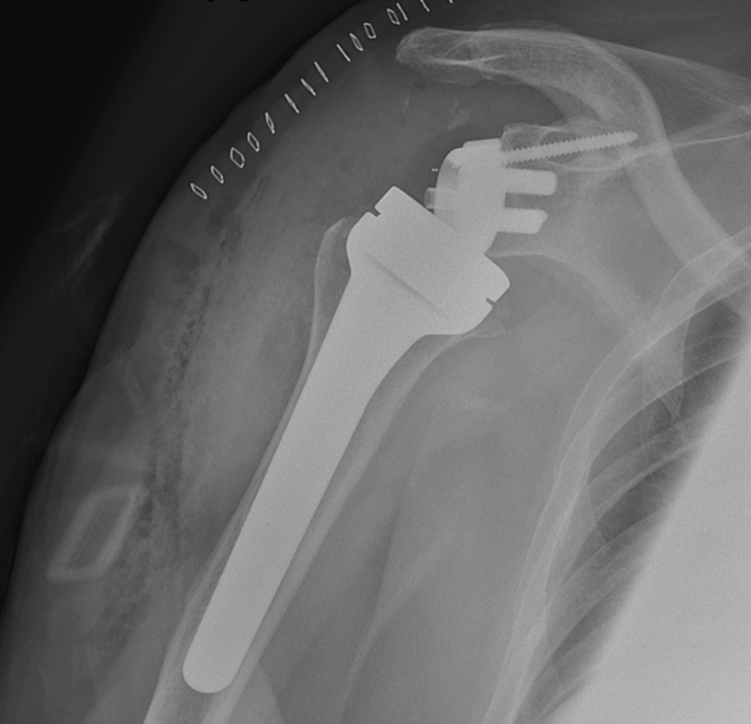

Heelkundige behandeling: prothese

Als de breuk zodanig complex is dat osteosynthese geen geschikte oplossing is, of als er een slechte botkwaliteit is, zal er voor een prothese gekozen worden. Er zijn twee types prothesen: de anatomische schouderprothese (hemiprothese) en de reversed schouderprothese (omgekeerde schouderprothese).

Bij de anatomische schouderprothese worden de schouderkop en schouderkom vervangen door een prothese. De voorwaarde hiervoor is dat de omliggende spieren en pezen die de schouderkop en -kom samenhouden (de rotator cuff) nog intact zijn.

Reversed schouderprothese

Bij complexe breuken waarbij de rotator cuff ook beschadigd is, wordt gekozen voor de reversed schouderprothese (omgekeerde schouderprothese). Hierbij worden ook de schouderkop en schouderkom vervangen door een prothese, maar wordt er in de holle schouderkom een bol geplaatst en wordt er in de bovenarmkop een kom gemaakt. Dat is eigenlijk het omgekeerde van de natuurlijke situatie, vandaar de naam 'omgekeerde schouderprothese'. Op die manier kan de arm toch bewogen worden zonder gebruik te maken van de omliggende, beschadigde spieren en pezen.